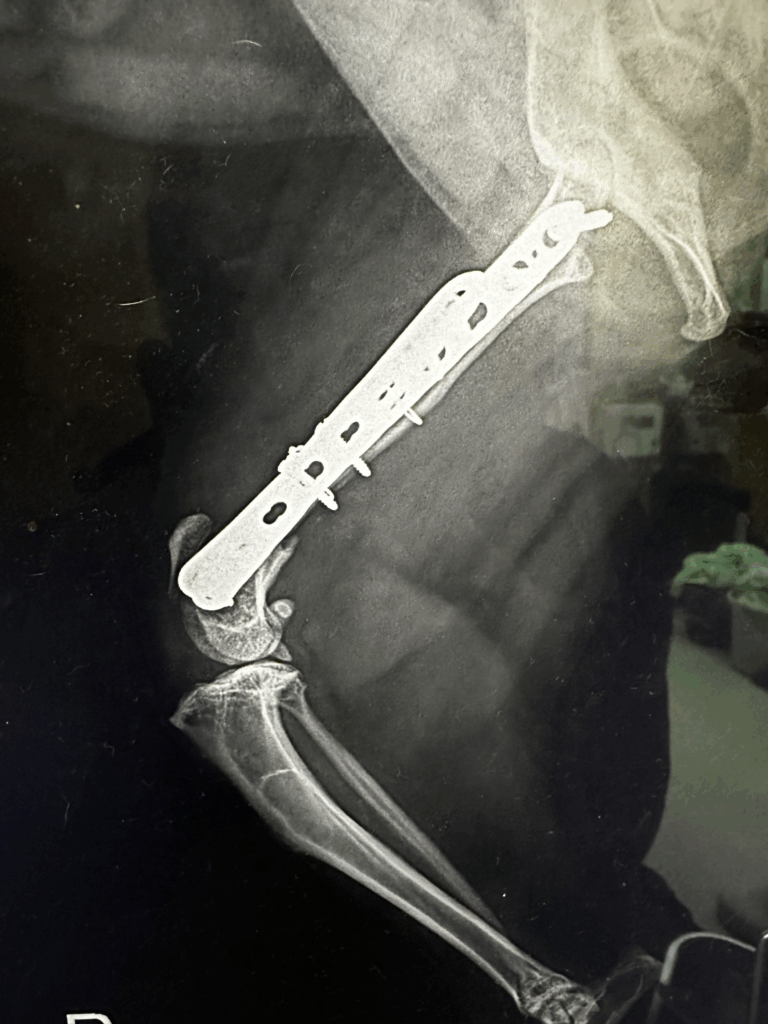

自宅のキャットタワーから転落してしまい、大腿骨が骨折しました。当院へ来院。

整形外科専門外来でプレート固定術を行ったところ、現在は元気に走り回れるようになりました。

レントゲンだけでなく、必要に応じてCT撮影を行い、骨折の状態を立体的に把握できます。 - 専用の手術器具とインプラント

プレート、スクリュー、ピンなど、その子に合わせた最適な固定方法を選択可能。 - 経験豊富な整形外科医